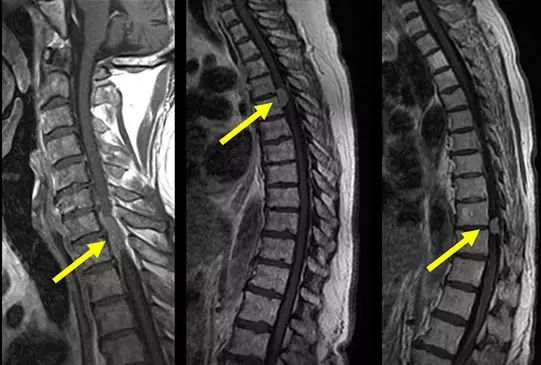

虽然脑膜瘤可发生在脊髓全部水平,但约80%位于胸段。这些脑膜瘤常表现出脊髓病的症状和体征,如渐进式步态和感觉障碍,并伴有上运动神经元病变表现。鉴别诊断应该包括神经鞘瘤、神经纤维瘤和转移瘤。下图显示的是三例不同患者的增强MRI扫描T1WI矢状位图像。从左至右,脑膜瘤分别位于C7-T1,T5-6和T10-11。影像学特点可以帮助鉴别神经鞘瘤与脑膜瘤;神经鞘瘤很少位于脊髓后,常常伴有神经孔扩大。脑膜瘤更有可能出现明显的硬脑膜附着。